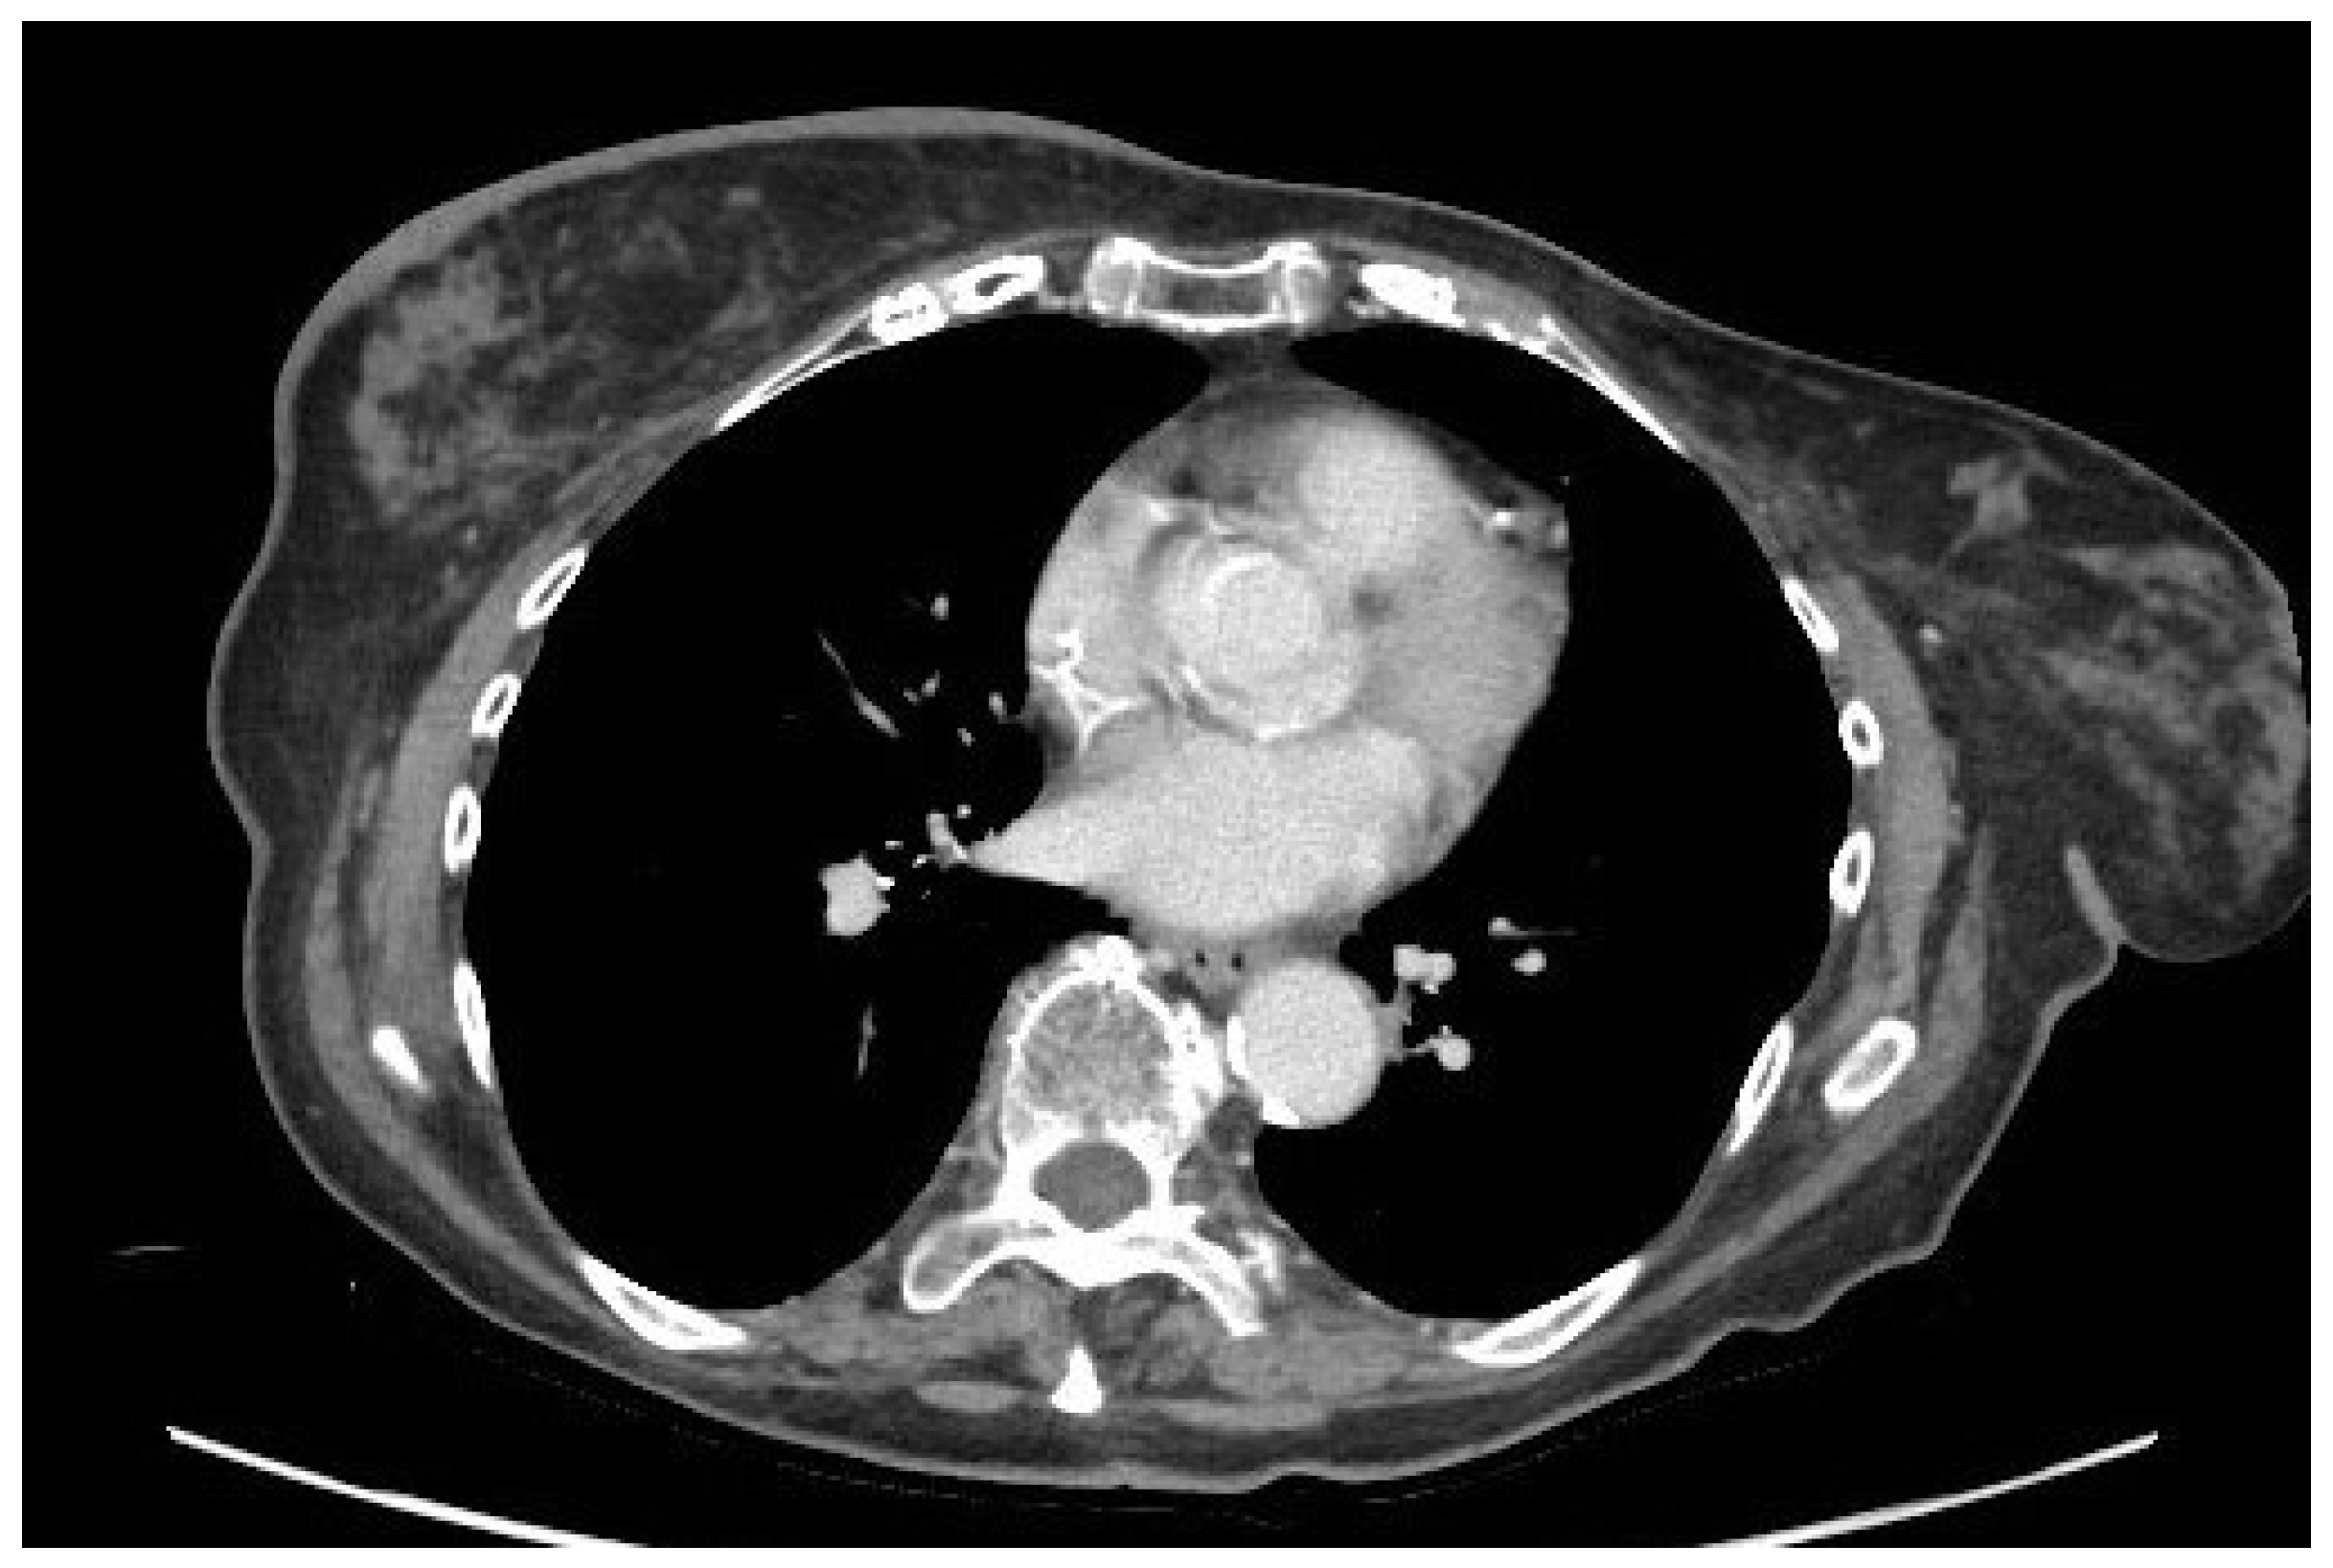

4.4. Computed Tomography